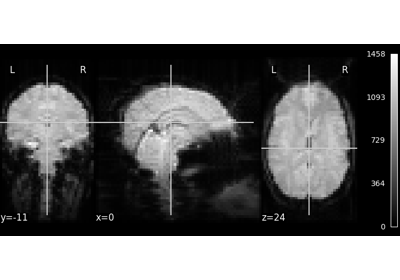

Plot cuts of an EPI image.

By default 3 cuts: Frontal, Axial, and Lateral.